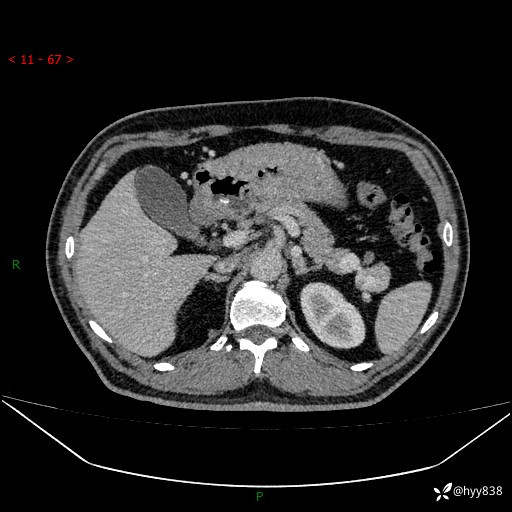

增强动脉期

静脉期